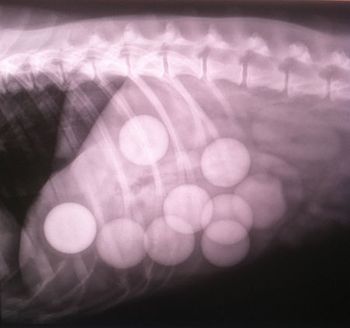

That x-ray box in your exam room can perform a double duty.

Martin, a 4-year-old Labrador, was looking forward to a great afternoon after a Sunday morning on the driving range. But this dog brought home a gift from the fun outing. After surgical removal of the golf balls, Martin made a full recovery.